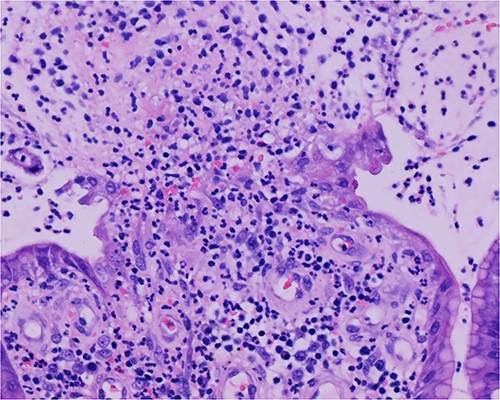

Histologic sections of the polyps demonstrated benign gastric hyperplastic polyps with acute and chronic gastritis (Fig. 2). Portions of the gastric polyps and adjacent mucosa were covered by inflammatory cell exudate (Fig. 3). Higher magnification revealed conspicuous volcanic-like eruption of the exudate, reminiscent of pseudomembranous gastritis (Fig. 4). Alcian yellow and GMS stains were negative for Helicobacter pylori and fungal organisms, respectively.

Biopsy of the polyp, covered in part by pseudomembranous inflammatory exudate.